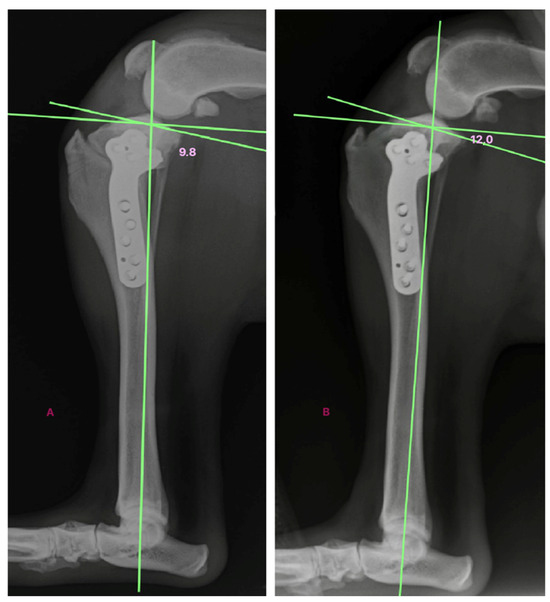

| Dog 5 | 5.4 | 6.7 | 8.6 | 9.8 | 4.4 |

| Dog 6 | 9.8 | 10.9 | 11.8 | 12 | 2.2 |